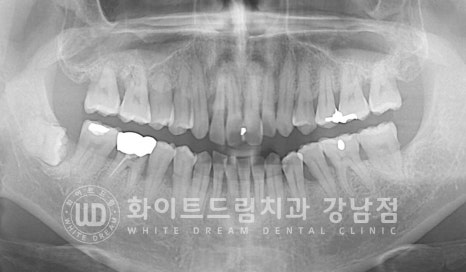

우선 흔들리는 치아를 발치한 후 바로 임플란트를 식립했고 염증으로 녹은 잇몸뼈는

추가적인 뼈이식을 통해 보강하여 치료를 진행하게 되었습니다.

12번 임플란트가 골 유착되는 회복 기간 동안에는 남은 11, 21번 치아의 신경치료와

잇몸치료를 동반하게 되었습니다.

치료가 마무리되기 전까지는 임시치아를 세팅해 드려

일상생활에 지장이 없도록 처치해 드렸습니다.